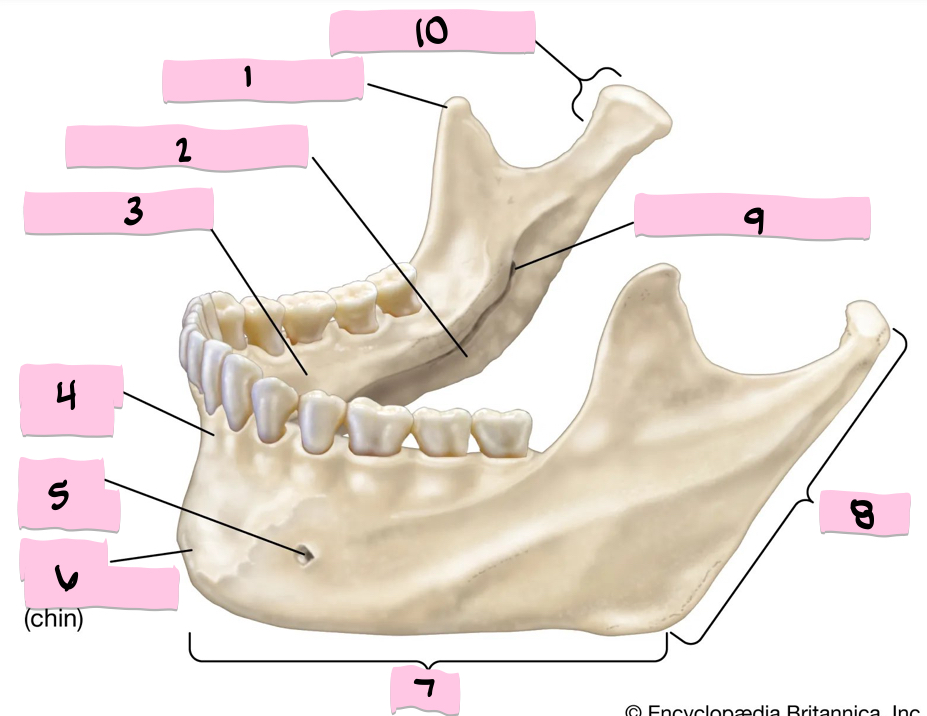

What is 1 pointing to?

Coronoid process

What is 2 pointing to?

Submandibular fossa

What is 3 pointing to?

Sublingual fossa

What is 4 pointing to?

Alveolar process

What is 5 pointing to?

Mental foramen

What is 6 pointing to?

Mental protuberance

What is 7 pointing to?

Body

What is 8 pointing to?

Ramus

What is 9 pointing to?

Mandibular foramen

What is 10 pointing to?

Condylar process